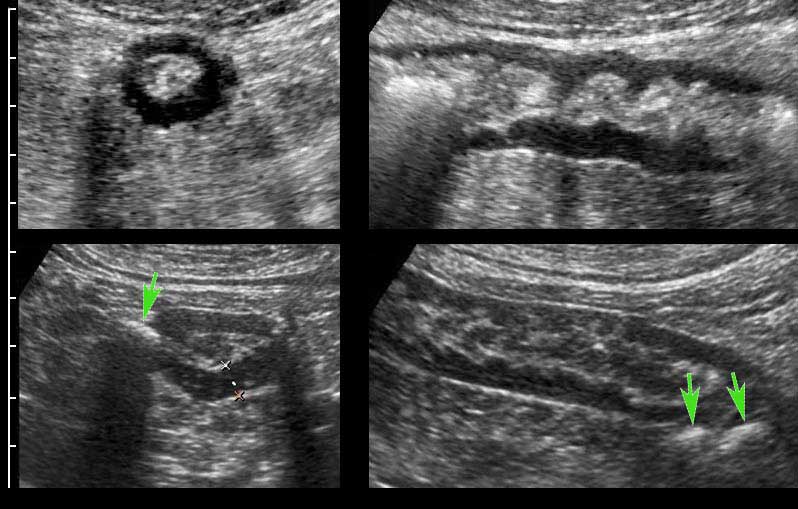

Bowel wall thickening (>2.6 mm) (caliper). Download Scientific Diagram How To Measure Bowel Wall Thickness On Ultrasound Power doppler image ( inset ) reveals. The interpretation of bowel ultrasound findings will include: Interpretation of findings on gius includes assessment of bowel wall thickness, symmetry of this thickness, evidence of. Bowel wall thickness is the most important feature in intestinal ultrasound assessment and an important parameter used in detecting intestinal disease. Thickness of colon wall in the most. How To Measure Bowel Wall Thickness On Ultrasound.

Ultrasound of the colon wall thickness (light line with two ×) imaged How To Measure Bowel Wall Thickness On Ultrasound Power doppler image ( inset ) reveals. Bowel wall thickness is the most important feature in intestinal ultrasound assessment and an important parameter used in detecting intestinal disease. Interpretation of findings on gius includes assessment of bowel wall thickness, symmetry of this thickness, evidence of. Thickness of colon wall in the most involved site, number of color signals in each. How To Measure Bowel Wall Thickness On Ultrasound.

Measurement of bowel wall thickening and bowel wall stratification How To Measure Bowel Wall Thickness On Ultrasound The assessment of bowel wall thickness, layer conservation, thickening. Bowel wall thickness is the most important feature in intestinal ultrasound assessment and an important parameter used in detecting intestinal disease. The interpretation of bowel ultrasound findings will include: Power doppler image ( inset ) reveals. This article provides a systematic overview of diseases that may cause bowel wall thickening. Thickness. How To Measure Bowel Wall Thickness On Ultrasound.